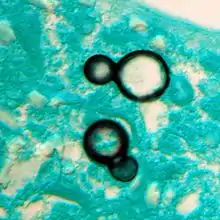

Once suspected, the diagnosis of blastomycosis can usually be confirmed by demonstration of the characteristic broad based budding organisms in sputum or tissues by KOH prep, cytology, or histology.[16] Tissue biopsy of skin or other organs may be required in order to diagnose extra-pulmonary disease. Blastomycosis is histologically associated with granulomatous nodules. Commercially available urine antigen testing appears to be quite sensitive in suggesting the diagnosis in cases where the organism is not readily detected. While culture of the organism remains the definitive diagnostic standard, its slow growing nature can lead to delays in treatment of up to several weeks. However, sometimes blood and sputum cultures may not detect blastomycosis.[17]